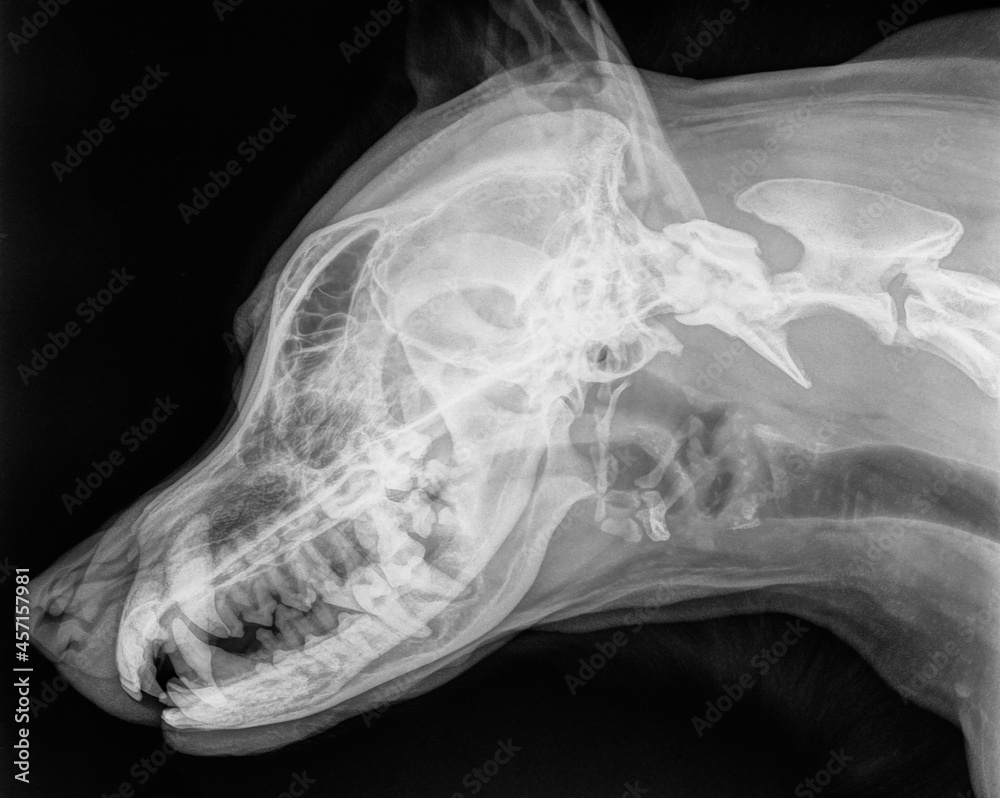

From stock.adobe.com

Xray of the skull of a large dog, side view. Black and white photo Stock Photo Adobe Stock Dog Jaw X Ray — what causes tmj disorders in dogs? Tmj dysplasia tmj dysplasia is a rare developmental disease reported in basset hounds, cavalier king charles spaniels, dachshunds, and certain feline breeds (i.e., persians). jaw lesions appear on dental radiographs as areas of bone loss of inflammatory, cystic, or neoplastic origin. general signs of osteomyelitis include lameness and pain. . Dog Jaw X Ray.